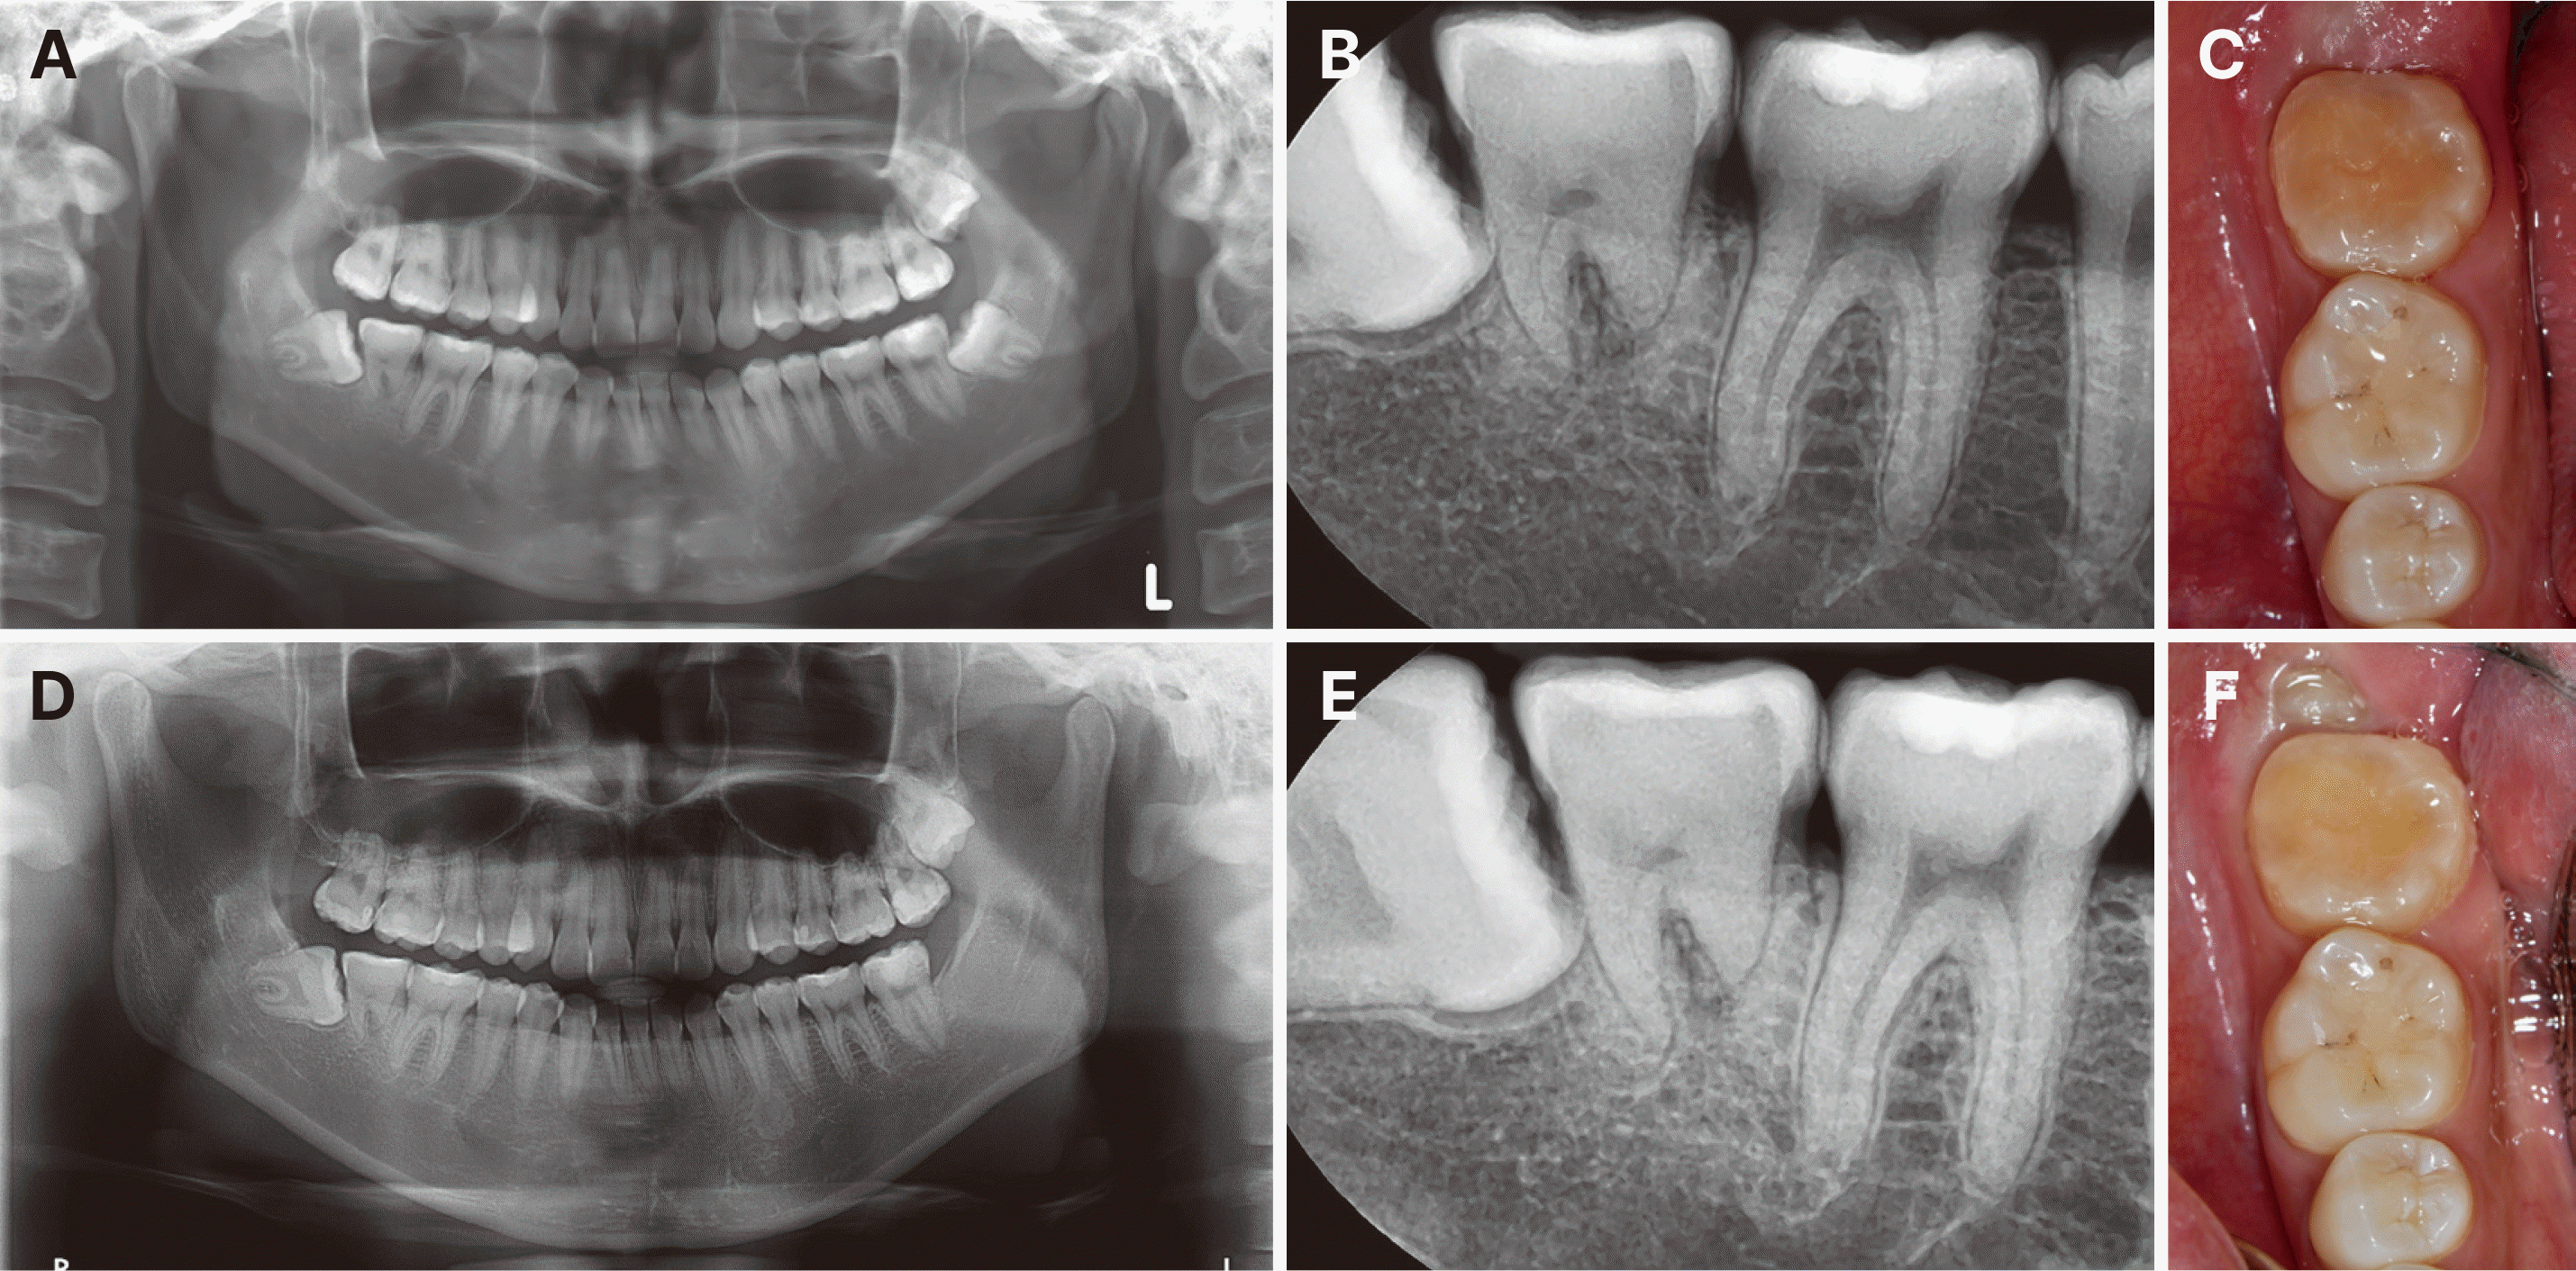

수술 10일 후 임상검사에서 정상적인 초기 치유 양상이 관찰되어 강선고정은 제거하였다(Fig. 3A - 3C). 이후 1.5개월 시점의 추적 관찰에서도 양호한 치유 상태가 확인되었다(Fig. 3D). 이후 3개월, 6개월, 1년 간격으로 정기검진을 시행하였다. 술 후 3개월째 임상검사에서 3 mm 이내의 치주낭 깊이와 정상적인 동요도를 보였으며, 냉검사에 양성 반응을 나타내어 치수 생활력이 회복되었음을 확인할 수 있었다. 수술 2년 4개월 시점의 방사선 사진에서 완전한 치근 형성이 확인되었다(Fig. 4A - 4C). 수술 뒤 3년 10개월 시점이 이식치아의 후방 제3대구치가 맹출하여 환자에게 하악 우측 제3대구치의 발치를 권고하였다(Fig. 4D - 4F).

Fig. 4

Progressive healing and periodontal ligament adaptation phase. Follow-up at 2 years and 4 months after surgery showing continued root development and periodontal healing: (A) Panoramic radiograph demonstrating continued root formation, (B) Periapical radiograph showing normal periodontal ligament space, (C) Clinical photograph showing healthy gingival condition. Follow-up at 3 years and 10 months after surgery: (D) Panoramic radiograph showing complete root formation and mesially angulated eruption of mandibular right third molar toward the transplanted tooth, (E) Periapical radiograph confirming normal periodontal space and bone healing, (F) Clinical photograph showing stable occlusion and gingival health.